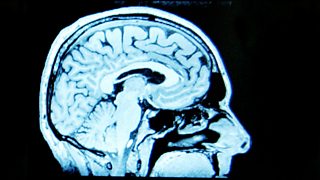

When I was at medical school we were taught that we were born with all the brain cells we would ever have, and that after middle age it was downhill from then on. But we now know that this isn’t true. Today technologies like MRI and MEG scanning mean that we can peer inside the living brain and take a look at how it functions in ways that were not possible even a decade ago. This research is shedding light on something that scientists call ‘neuroplasticity’ – the idea that our brains keep on changing, and that we go on growing new brain cells, and making new brain connections, throughout our lives.